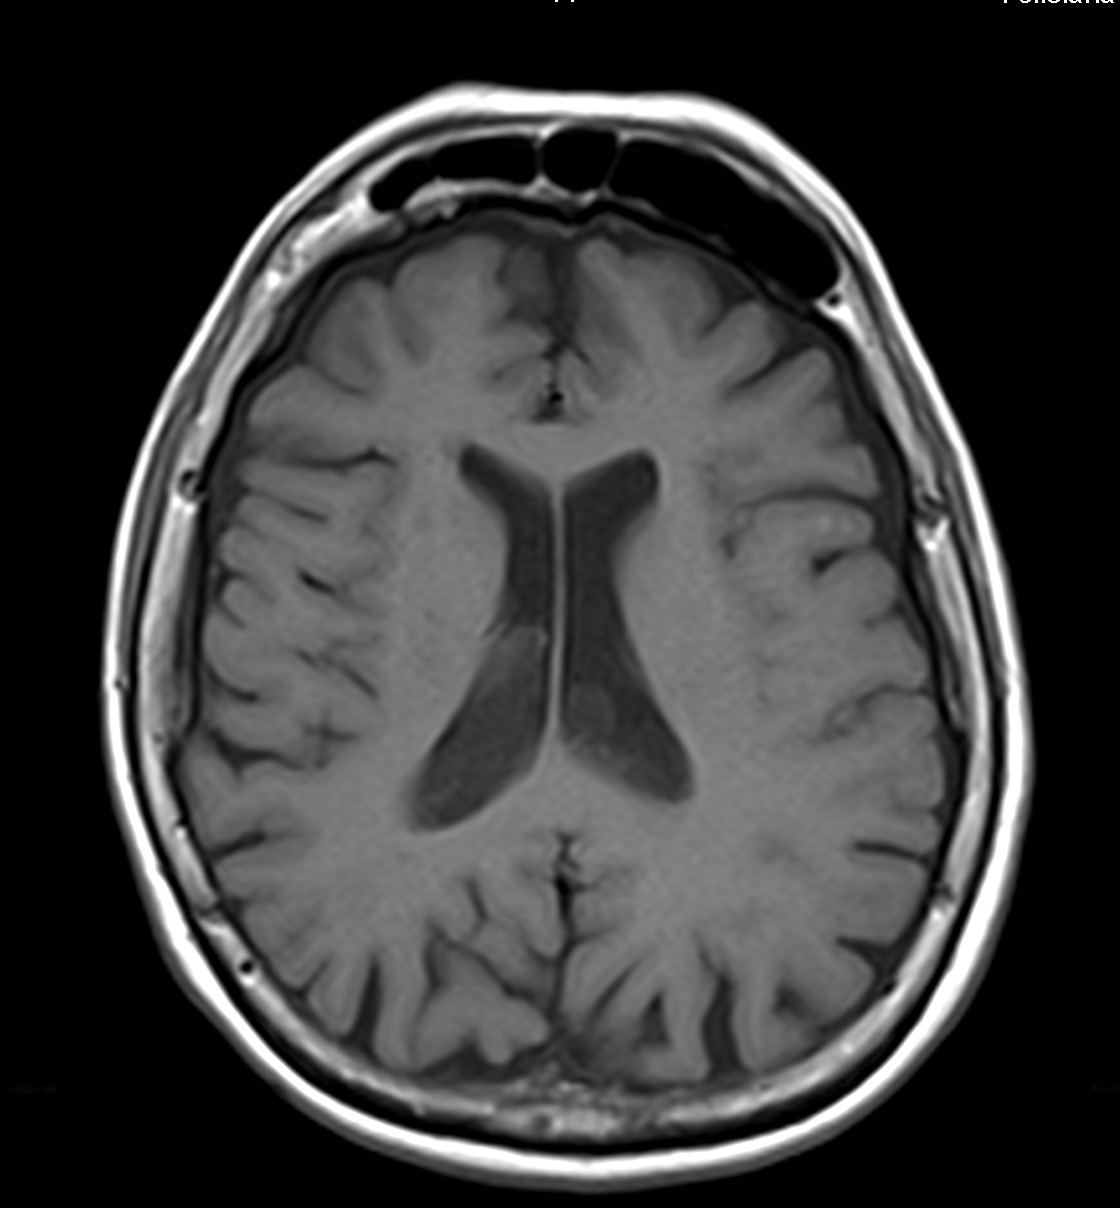

Son pseudolesiones frecuentemente observadas en estudios de neuroimagen.

Sus principales características son:

✔ Lesiones intraventriculares

✔Bilaterales

✔65% restringen en la secuencia de difusión

✔ Realce variable posterior a la administración de medio de contraste

✔ No hay edema del parenquima adyacente

NO DEBEN CONFUNDIRSE CON LESIONES TUMORALES INTRAVENTRICULARES!!!!